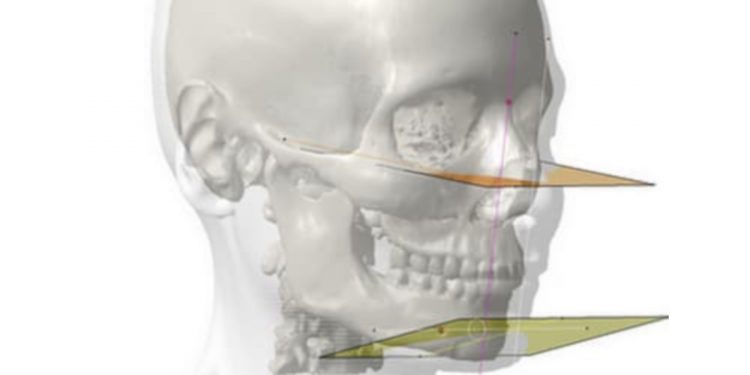

Planificación quirúrgica 3D

Desvelamos cómo aprovechar la tecnología de impresión 3D en el sector médico aplicada a la planificación quirúrgica.

Desvelamos cómo aprovechar la tecnología de impresión 3D en el sector médico aplicada a la planificación quirúrgica.

Simulador de una prótesis de resuperficialización de cadera. Ejemplo de planificación quirúrgica y medicina personalizada.